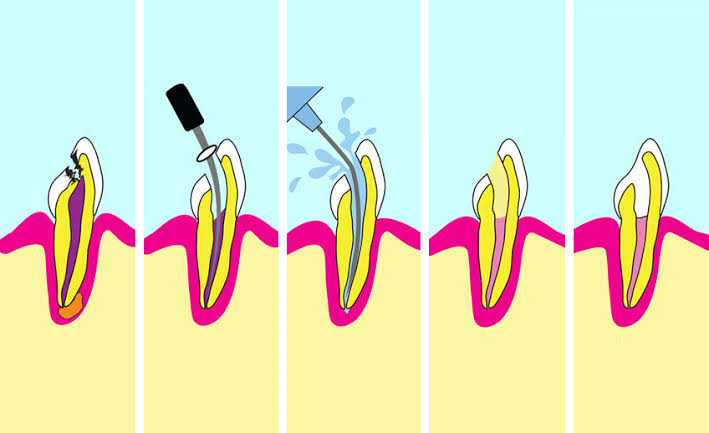

Painless, single-visit therapy using advanced rotary instruments to save infected teeth from extraction.